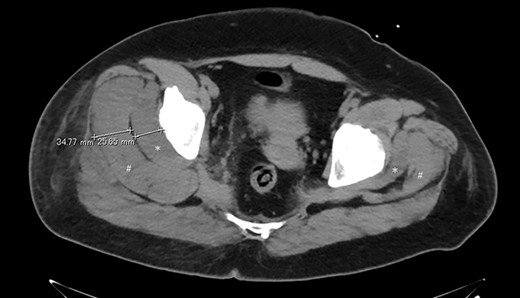

On X + 1, the day after surgery, the pain in the greater trochanter was less than that immediately after surgery, and the patient was able to hold on and walk. The patient’s resting pain was 78 mm on a visual analog scale (VAS), with an immediate postoperative pain of 100 mm. The pain on the extension of the buttock (hip adduction added to the straight leg rising position) was mild. Blood tests revealed markedly elevated creatine kinase (CK) of 67 871 IU/l. No myoglobinuria was observed. We suspected GCS; however, since the patient’s clinical symptoms improved, we decided to follow up by administering adequate hydration with supplemental fluids. At X + 2 days postoperatively, her pain at rest increased to 95 mm on the VAS, making it difficult for the patient to walk. Pain on the extension of the buttock also increased, but there was no evidence of nerve palsy and circulatory disturbance. CK levels1 in blood tests decreased to 26 357 IU/l. Computed tomography (CT) imaging showed a marked increase in gluteal muscle thickness in the axial view. The gluteus minimus was 26 mm and the gluteus medius was 35 mm, which was approximately three times thicker than that of the healthy side (Fig. 2). Based on the above, we made a diagnosis of GCS and decided to perform urgent fasciotomy. Under general anesthesia, the intramuscular compartment pressure was 72 mmHg on the affected side (healthy side, 26 mmHg; diastolic pressure, 50 mmHg). In the left lateral position, the patient was deployed using posterior approach. The fascia was incised with a shear knife, and the internal tension of the muscles was very high. The musculature of the medius and minimus fasciae was grossly dark red. The patient’s postoperative pain improved, and on X + 3 days, the pain on the buttock extension was relieved. A history of VAS and CK until the discharge is shown in Fig. 3. The symptoms disappeared 2 months after surgery.

Axial view of the maximum thickness of the left gluteus minimus and medius muscles on CT. The right side is about three times thicker than the left side with respect to the gluteus minimus (*) and the gluteus medius (#).